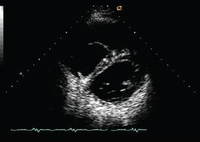

Short axis echocardiographic view in a patient with pulmonary regurgitation following repair of tetralogy of Fallot. The patient has a restrictive right ventricle, and short axis echocardiographic view reveals a small right ventricle

From: Chaturvedi RR, Redington AN. Heart. 2007 Jul;93(7):880-9; used with permission